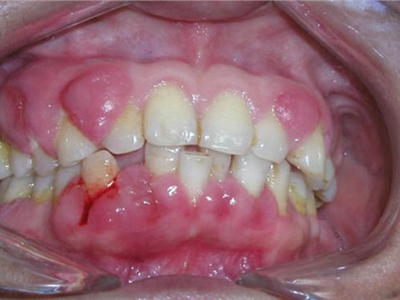

牙龈瘤多发于女性,以青年及中年人为常见,多发生于牙龈乳头部,位于唇、颊侧者较舌、腭侧者多,最常见的部位是前磨牙区。肿块较局限,呈圆形或椭圆形,有时呈分叶状,大小不一,直径由几毫米至数厘米。

肿块有的有蒂,如息肉状;有的无蒂,基底宽广,生长较慢,但在女性妊娠期间可能迅速增大。较大的肿块可以遮盖一部分牙及牙槽突,表面可见牙压痕,易被咬伤而发生溃疡,伴发感染。随着肿块的增长,牙槽骨壁逐渐被破坏,牙可能发生松动、移位。

局部刺激因素,包括菌斑、牙石、食物嵌塞或不良修复体的刺激,引起局部长期慢性炎症,致使牙龈结缔组织形成反应性增生物,即牙龈瘤。此外,牙龈瘤可能和内分泌有关,妇女怀孕期间容易发生牙龈瘤,而分娩后会缩小或停止生长。